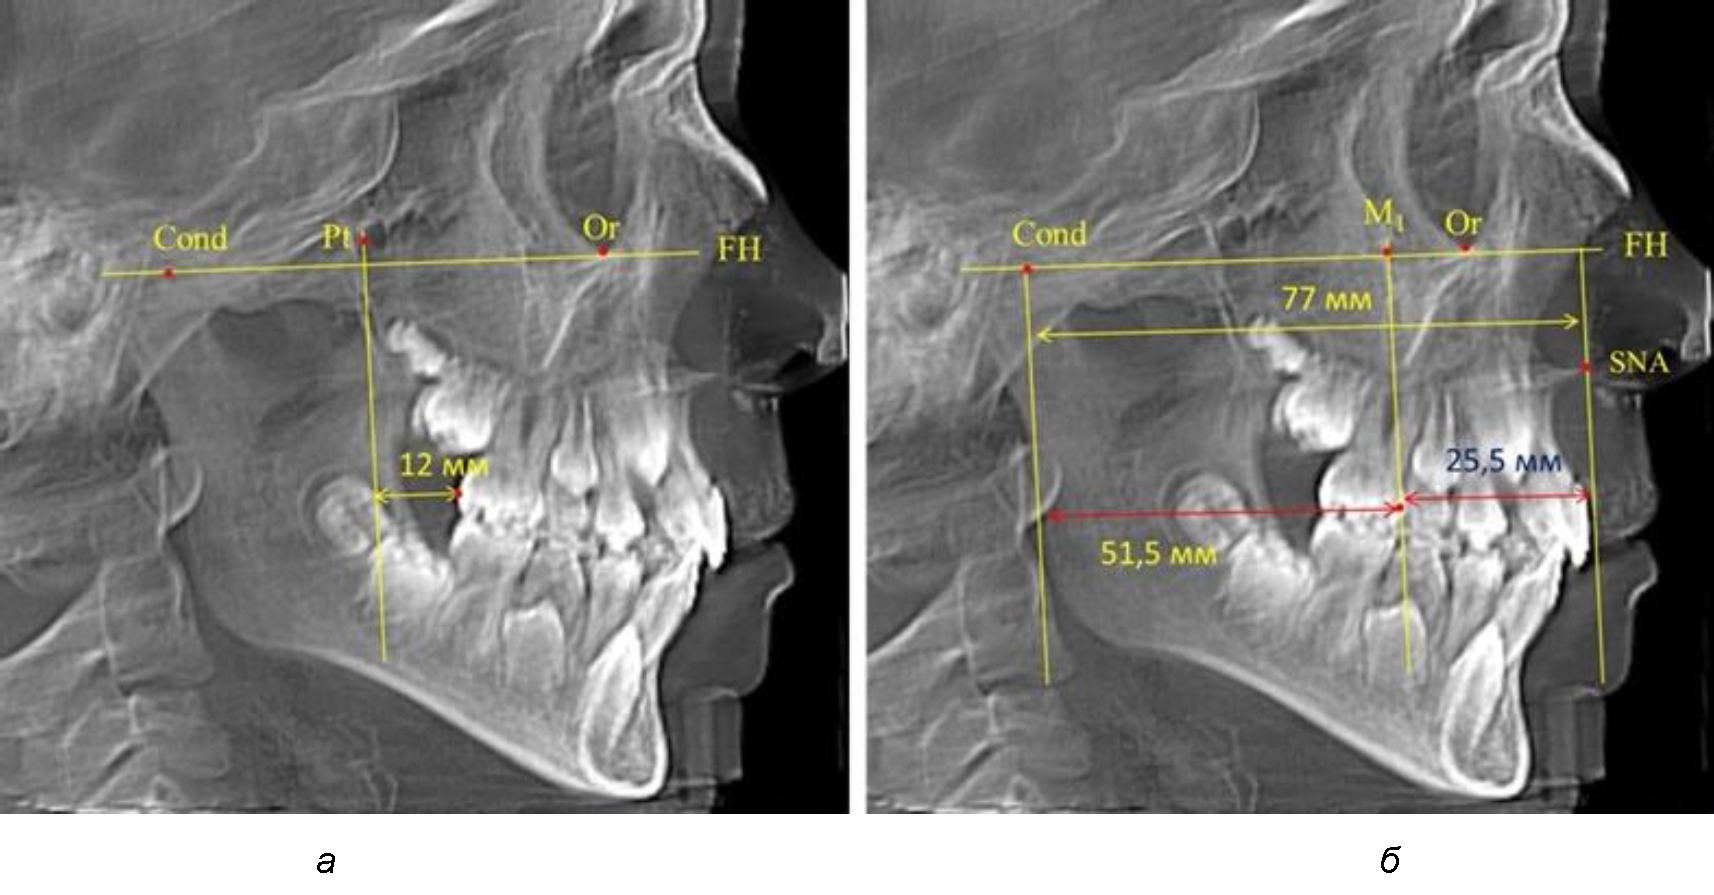

При проведении анализа к Франкфуртской горизонтали проводили передний и задний перпендикуляры. Передний спинальный перпендикуляр проходил через выступающую точку передней носовой ости (spina nasalis anterior – SNA), а задний суставной перпендикуляр опускали из кондилярной точки Cond. Молярный перпендикуляр проводили через медиальную поверхность первого постоянного моляра. Указанная вертикаль отделяла замещающие зубы постоянного прикуса от добавочных зубов (постоянных моляров), что вполне логично для анализа положения первых постоянных моляров в гнатическом комплексе (рис. 1).

Рис. 1. Метод определения положения первых верхних моляров по Ralph E. McDonald (а) и по предложенному методу (б)